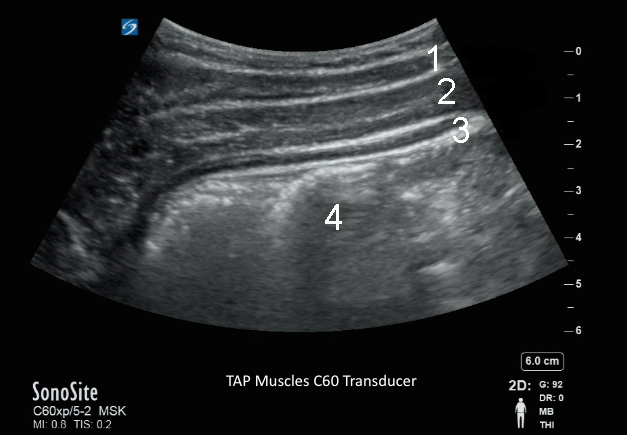

Muscles abdominaux visualisés par sonde C60

1. Muscle oblique externe de l'abdomen

2. Muscle oblique interne de l'abdomen

3. Muscle transverse

4. Cavité péritonéale